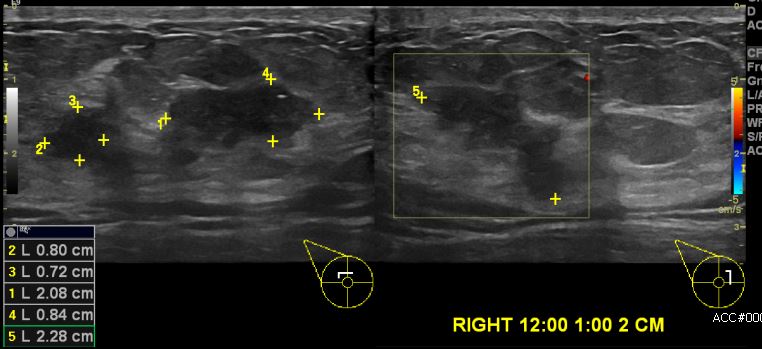

상기환자 건강검진상 이상 소견으로 내원하신 40대 여성분으로 우측 12시에서1시

방향에서 2cm 떨어진 거리의 의심스러운 혹 조직검사 시행하여 우측 침윤성 유관암

진단되었습니다.